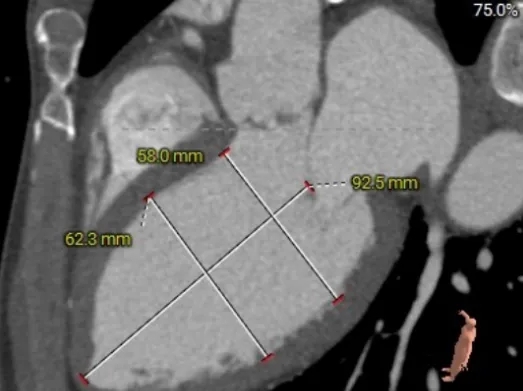

术前CT分析

收缩期主动脉瓣环周长径27.8mm

收缩期LVOT周长径28.2mm

STJ周长径29.6mm

升主动脉周长径31.9mm

左室舒末内径增宽

外周入路条件尚可